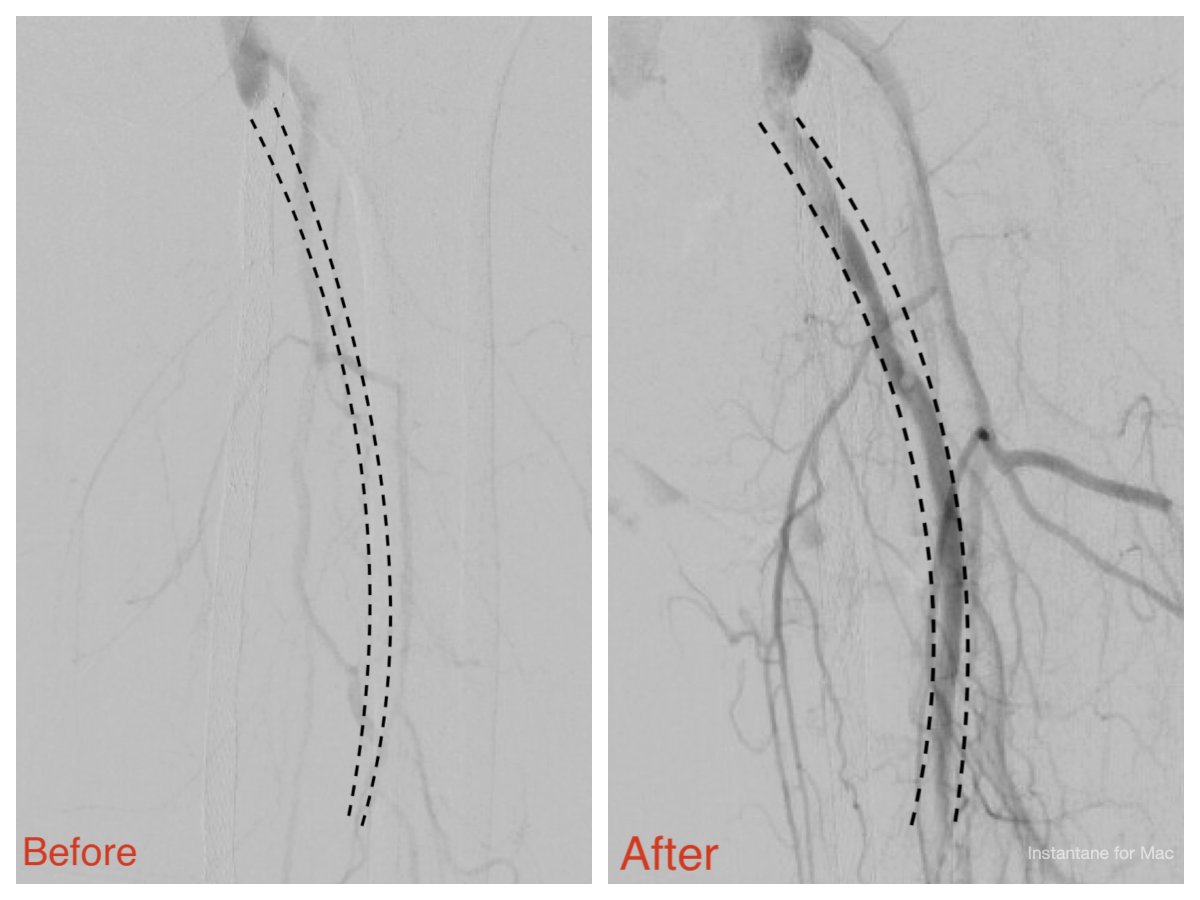

#PTAB doesn’t have to be long or complicated. Once you’ve done a few, sub-1 hour cases are the norm. Wrapped one up today in just 38 minutes @Phantom495 @MarcoShakerIC @DeanFerreraDO @JodiWeinzetl1 @endologix

We completed the first 2 perc bypass in Illinois w #Detour @endologix Excited for this groundbreaking technology to be in the hands of #limbsalvage docs around the globe. @ShawnPenn33 @DeanFerreraDO @Abd_Alrifai @MarcoShaker @tlevin @advocatehealth